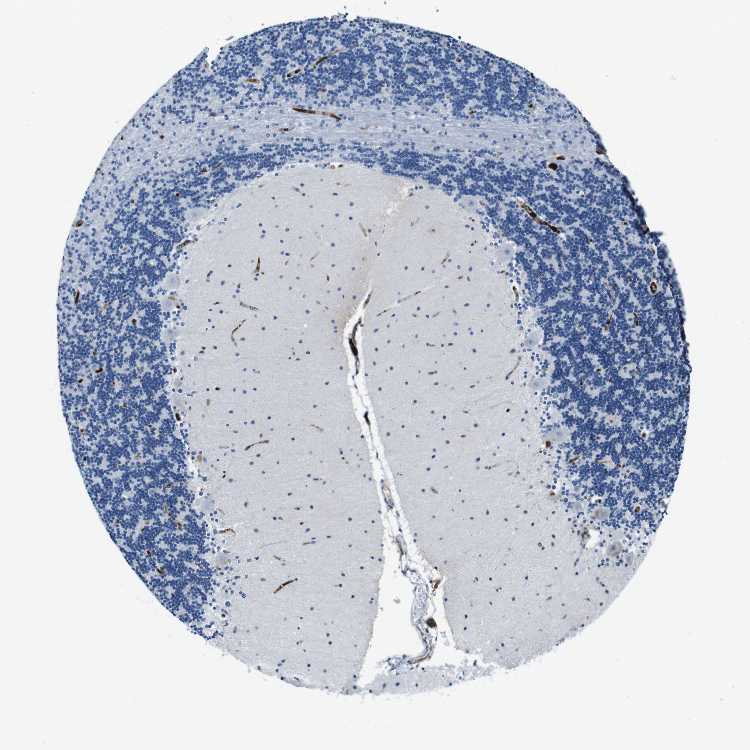

BRAIN CEREBELLUM Show tissue menu

CEREBELLUM - Expression summary

CEREBELLUM - Antibody stainingi

Antibody staining in the annotated cell types in the current human tissue is reported as not detected, low, medium, or high, based on conventional immunohistochemistry profiling in selected tissues. This score is based on the combination of the staining intensity and fraction of stained cells.

Each image is clickable and will lead to virtual microscopy that enables deeper exploration of all samples and also displays staining intensity scores, fraction scores and subcellular localization as well as patient and tissue information for each sample.

Antibody CAB012703

Purkinje cells Not detected

Cells in granular layer Not detected

Cells in molecular layer Not detected